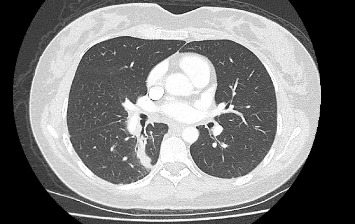

由于靶向治疗的安全性数据有限,妊娠期间癌基因驱动的非小细胞肺癌(NSCLC)的管理面临着独特的挑战。间变性淋巴瘤激酶(ALK)重排非小细胞肺癌是一种罕见的疾病,但越来越多的人认识到它存在于年轻女性中,包括怀孕期间。在这里,我们报告一例37岁的女性在她的第一次怀孕期间被诊断为转移性alk重排NSCLC,她开始使用alectiinib。在此之后,她成功地进行了第二次怀孕,同时接受了alectinib治疗(在妊娠6-10周期间暂停,以避免器官发生的关键时期)。两次怀孕都产生了健康的婴儿,没有并发症或发育迟缓的迹象。本病例强调了多学科方法的重要性,包括肿瘤学、母胎医学、临床遗传学、产科医学和产科,以平衡孕产妇癌症控制和胎儿健康。虽然临床前研究表明阿勒替尼有致畸风险,但这一病例和其他报道的病例表明,在仔细计划的情况下,妊娠期间使用阿勒替尼是安全的。本例胎盘病理检查未发现恶性细胞,母体疾病得到控制。随着靶向治疗延长晚期非小细胞肺癌的生存期,更多的患者可能会考虑怀孕,这强调了需要强有力的证据来指导治疗决策。该病例提供了越来越多的证据,支持alk重排NSCLC患者使用alectinib等靶向治疗来管理妊娠的可行性,同时强调了对暴露后代进行长期随访的重要性。

The management of oncogene-driven non-small cell lung cancer (NSCLC) during pregnancy presents unique challenges due to limited safety data on targeted therapies. Anaplastic lymphoma kinase (ALK)-rearranged NSCLC is a rare but increasingly recognized entity in young women, including during pregnancy. Here, we report the case of a 37-year-old woman diagnosed with metastatic ALK-rearranged NSCLC during her first pregnancy, who was commenced on alectinib. Following this, she had a successful second pregnancy whilst being treated with alectinib (withheld during weeks 6-10 of gestation to avoid the critical period of organogenesis). Both pregnancies resulted in healthy infants with no complications or evidence of developmental delays. This case highlights the importance of a multidisciplinary approach involving oncology, maternal-fetal medicine, clinical genetics, obstetrics medicine, and obstetrics to balance maternal cancer control and fetal health. While preclinical studies of alectinib suggest teratogenic risks, this and other reported cases demonstrate its potential for safe use during pregnancy with careful planning. Pathological examination of the placenta in our case revealed no malignant cells, and maternal disease remained controlled. As targeted therapies extend survival in advanced NSCLC, more patients may contemplate pregnancy, emphasizing the need for robust evidence to guide treatment decisions. This case contributes to the growing body of evidence supporting the feasibility of managing pregnancy in patients with ALK-rearranged NSCLC using targeted therapies like alectinib, while underscoring the importance of long-term follow-up for the exposed offspring.